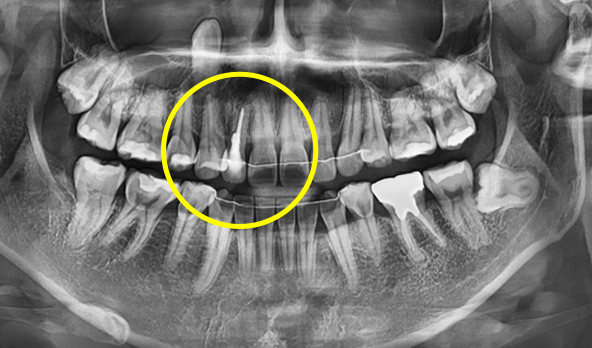

수술할 부위 치아 주변의 치주골 손상이 적은 경우

발치하는 치아 뿌리 끝 주변의 잇몸뼈가 튼튼한 경우

식립할 부위에 뼈의 양이 충분한 경우

발치 및 식립 부위에 염증이 적거나 거의 없는 경우

하루 완성 임플란트는 환자분의 잇몸뼈 상태에 따라

수술 가능 여부가 결정됩니다.